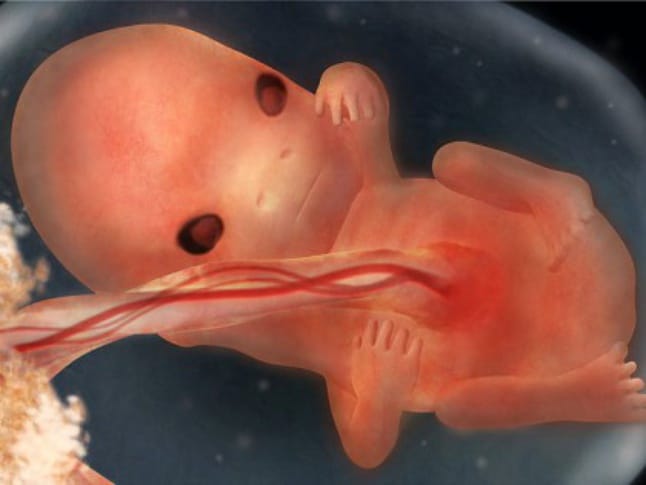

Беременность 9 недель: развитие плода внутри вас.

Можете ли вы поверить, что ваш ребенок все еще является эмбрионом всего лишь на одну неделю дольше и вскоре станет полноценным плодом? На 9 неделе беременности размер плода составляет примерно 2 см, что сопоставимо с обычной зеленой оливкой, но без мартини, пожалуйста.

Голова стала более прямой и развившейся к 8-9 неделям беременности, а уши продолжают расти, что делает ребенка более похожим на человека. Кроме того, уже видны пальцы, и все основные органы, такие как сердце, мозг, почки, печень и легкие, начали формироваться.

На 9-й неделе беременности руки и ноги вашего будущего плода начинают двигаться благодаря развитию крошечных мышц, хотя вы не ощутите его активность еще как минимум месяц или два.

Ниже представлены фотографии развития плода на 9 неделе беременности: